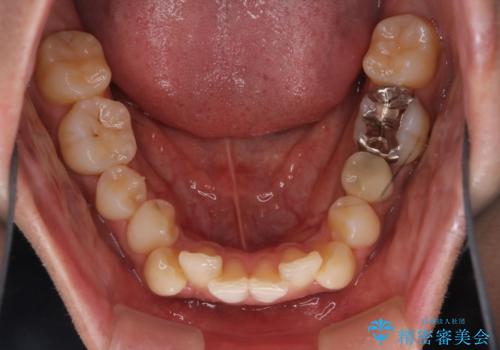

- 凸凹を治したいと来院された患者様です。

インビザラインにて、遠心移動を行いながら綺麗に配列することができました。

側切歯が低位の場合、反対咬合を改善した後に挺出させるのはワイヤーの方が適しています。